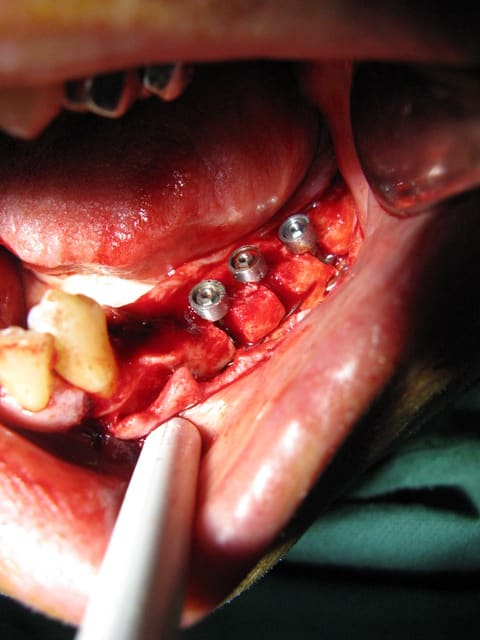

21 jours post-op

Oui patient très heureux même avec une petite "surcharge" implantaire selon certains ;-)

J'arrive un peu apres la bataille et je n'y connait rien en implants disques. Mais pourquoi en avoir mis secteur 3? parce que la trousse était sortie ou bien?